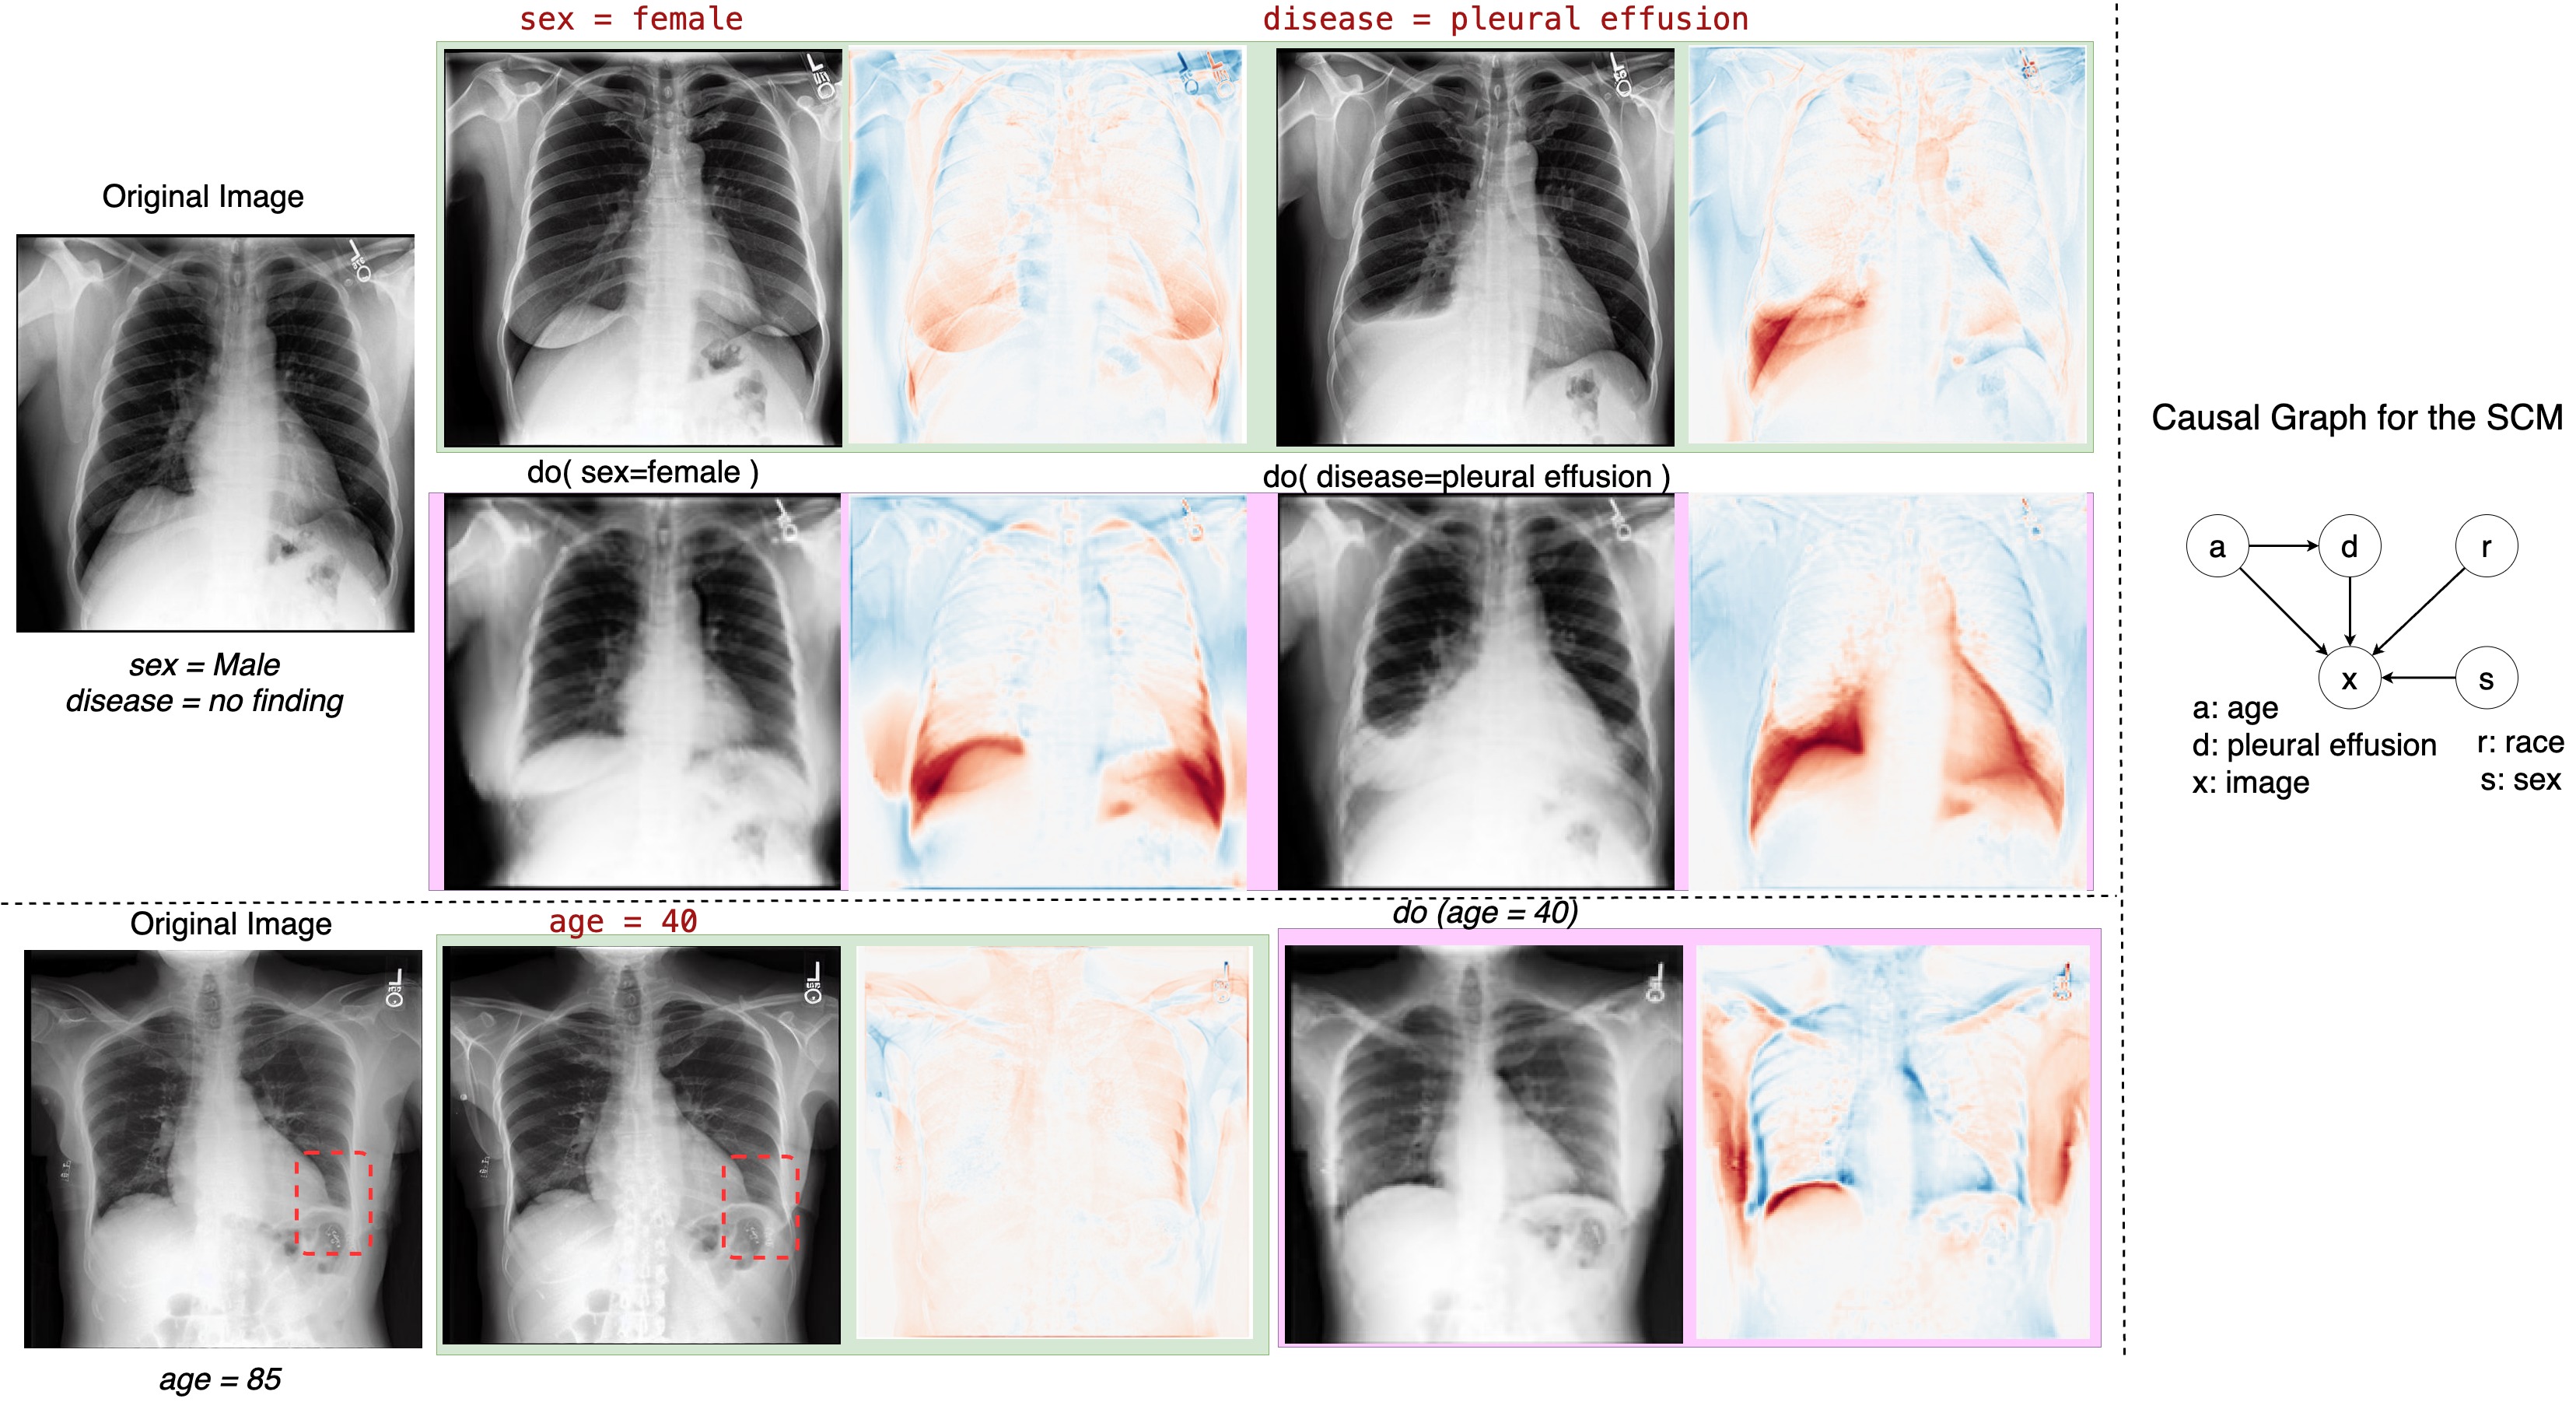

Our high-resolution results not only align with the baseline method to what interventions in the image should be made, but also maintain high fidelity to the original image 2. The baseline method’s pre-defined SCM includes an edge between age and pleural effusion, suggesting a potential causal relationship. Interestingly, without the need for an explicit SCM, the fine-tuned VLM also demonstrates an effect on pleural effusion when age is modified, Figure 2 Row 3. To further validate the viability of these generated counterfactual images, we consulted an expert radiologist for assessment.

Refer to caption

Figure 2: Comparison of counterfactual image generation results using [Row 1] proposed method vs. [Row 2] baseline, a SOTA method that employs an explicit SCM for generation. For the proposed method, counterfactual images are generated by modifying the text prompt against those generated by performing interventions using the do(.) operator in the baseline method for the attributes: sex and pleural effusion. [Row 3]: Modifications on the age attribute. According to the baseline pre-defined SCM, there exists an edge between age (a in the SCM) and pleural effusion (d), indicating a possible causal effect. Without defining the explicit SCM, proposed method demonstrates an effect on pleural effusion when modifying age. The regions anticipated to undergo changes are indicated in boxes. Note that the SCM method significantly alters the synthesis of CF images, resulting in changes to the subject’s anatomical structure.